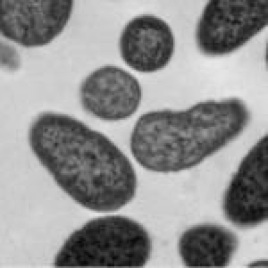

Some antimicrobial colonies form biofilms that create a defensive shield against antimicrobials. A typical biofilm formed by a Methicillin resistant Staphylococcus aureus (MRSA) colony is shown below. SilvaKlenz destroys the biofilm thereby reducing the effectiveness of this defense shield.

Normal MRSA biofilm

SilvaKlenz destroys biofilm and kills microbes